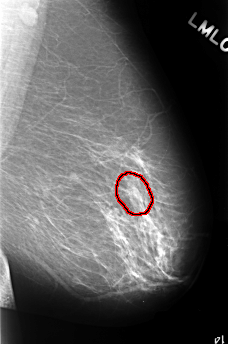

ics_version 1.0 filename C-0390-1 DATE_OF_STUDY 16 5 1996 PATIENT_AGE 66 FILM FILM_TYPE REGULAR DENSITY 2 DATE_DIGITIZED 9 11 1998 DIGITIZER LUMISYS LASER SEQUENCE LEFT_CC LINES 4424 PIXELS_PER_LINE 2928 BITS_PER_PIXEL 12 RESOLUTION 50 OVERLAY LEFT_MLO LINES 4472 PIXELS_PER_LINE 2952 BITS_PER_PIXEL 12 RESOLUTION 50 OVERLAY RIGHT_CC LINES 4520 PIXELS_PER_LINE 2960 BITS_PER_PIXEL 12 RESOLUTION 50 OVERLAY RIGHT_MLO LINES 4560 PIXELS_PER_LINE 2904 BITS_PER_PIXEL 12 RESOLUTION 50 OVERLAY |

FILE: C_0390_1.LEFT_MLO.OVERLAY TOTAL_ABNORMALITIES 1 ABNORMALITY 1 LESION_TYPE CALCIFICATION TYPE PLEOMORPHIC DISTRIBUTION CLUSTERED ASSESSMENT 4 SUBTLETY 4 PATHOLOGY BENIGN TOTAL_OUTLINES 1 BOUNDARY |